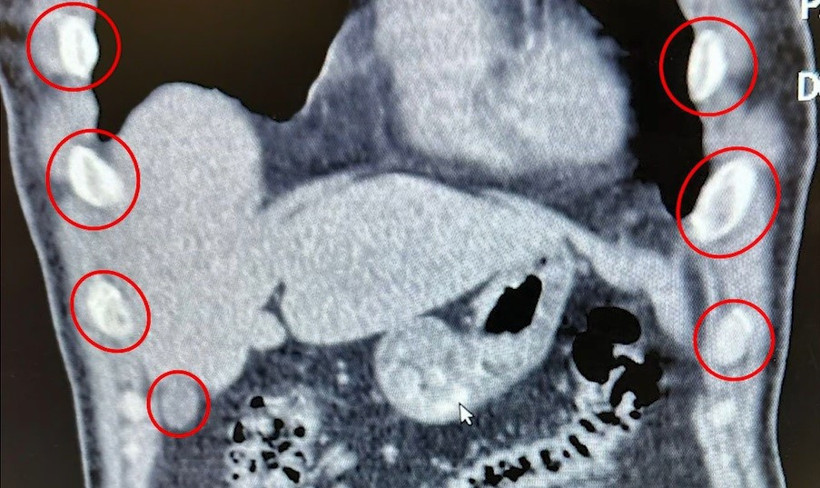

Düzenlenen narkotik operasyonunda yabancı uyruklu iki şüpheli, midelerinde taşıdıkları 136 uyuşturucu kapsülleriyle yakalandı.

Bitlis İl Emniyet Müdürlüğü Narkotik Suçlarla Mücadele Şube Müdürlüğü ekipleri, uyuşturucu ile mücadele kapsamında önemli bir operasyona imza attı. Tatvan ilçesinde durdurulan bir otobüste yolcu olarak seyahat eden yabancı uyruklu 2 kişi gözaltına alındı. Şahısların yapılan tıbbi müdahalesinde, yuttukları 136 kapsül halinde toplam 1 kilo 48 gram metamfetamin ele geçirildi. Uyuşturucu Madde İmal ve Ticareti suçundan gözaltına alınan zanlılar, çıkarıldıkları adli mercilerce tutuklanarak cezaevine gönderildi. Emniyet yetkilileri, vatandaşların huzur ve güvenliği için uyuşturucu madde imalatı, kaçakçılığı ve kullanımına karşı mücadelenin kararlılıkla sürdürüleceğini vurguladı.